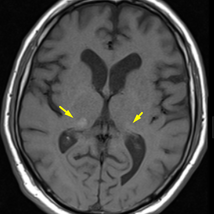

Fahr Disease and Fahr-like Calcifications (Secondary Fahr) – Professional Radiology Notes